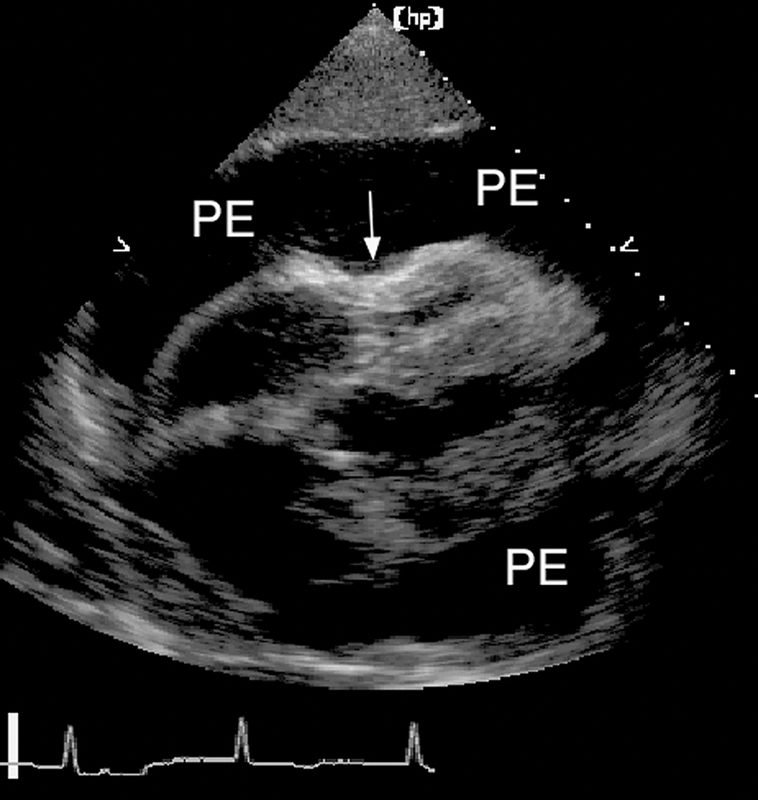

فحوصات تشخيصية لبعض امراض القلب والشرايين التاجية